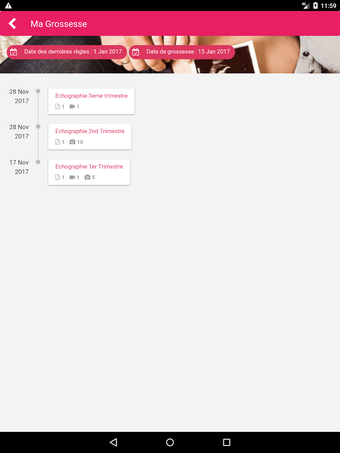

A free app for Android, by MonEcho.

MediFile is an application for medical professionals to manage all of their ultrasound images, reports, and other patient data in one place. The application allows them to scan, view, and save their files directly from their device. The application has the capability to upload reports to the server of the doctor or midwife, for whom the report was sent.

The main advantage of the application is that it makes it very easy for the medical professional to view and share their patient's data with their colleagues. It also facilitates the creation of a patient database and a communication channel for all of the medical professionals working on the same case.